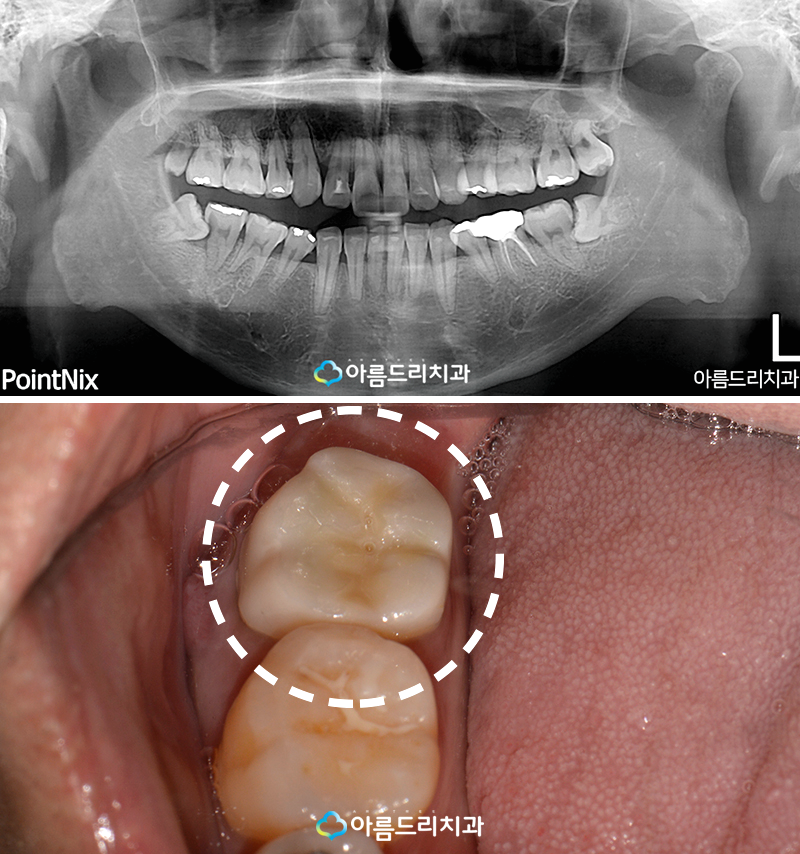

자연치아를 살리는 이 술식의 경우에는 심한 충치 혹은 잇몸질환으로 인해 치아의 뿌리에 염증이 발생한 병든치아에 마지막으로 해볼 수 있는 방법으로 임플란트의 기술이 아무리 발달했다고 하더라도 본인이 가지고 있는 자연치아의 높은 기능성과 자연스러움에 대해 완벽하게 대응하지는 못하기 때문에 아름드리에서는 한번 더 자연치아를 살리기 위한 이러한 진료를 진행하고 있으며 난이도가 높은 술식이라 할 수 있습니다.

과정에 대해 설명드리자면 치아의 뿌리 쪽 염증이 심한 경우에 환자분의 사례와 같이 치아를 뽑은 후 뿌리에 남아있는 염증을 제거하고 뿌리와 맞닿아 있는 부위에 퍼져 있는 염증 부분도 함께 제거합니다. 염증이 있던 치아의 뿌리 끝을 삭제하고 충전재료를 도포하여 처리한 후 다시 치아를 제자리에 식립하여 고정하게 됩니다. 이 모든 일련의 과정들은 15분내에 이루어져야만 성공율이 높습니다.